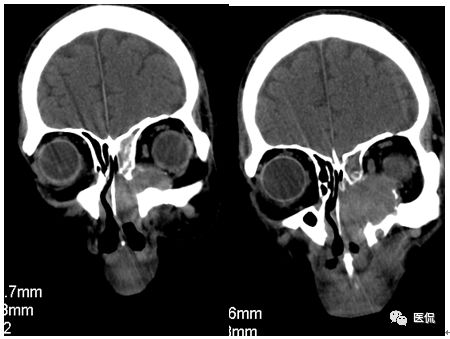

冠状位平扫

增强动脉期

CT平扫及增强示:左侧上颌窦及鼻腔可见软组织密度影,呈膨胀性生长,周围骨质压迫性吸收破坏,累及左眶,病灶密度不均匀,周边区可见点状钙化,增动脉期轻度强化,局部见小灶性稍高密度区,静脉期病灶内见不均匀明显强化,CT值最高达117HU,延迟期强化范围有所增大。

本例病灶较大,周围骨质可见吸收破坏,并累及眼眶,病灶内少量钙化,增强扫描具有一定特征性,表现为动脉期轻度强化,局部见小灶性稍高密度区,静脉期病灶局部呈明显强化,CT值最高达117HU,延迟期强化范围有所增大,呈延迟渐进性强化的特点,推测为病灶内出血所致。